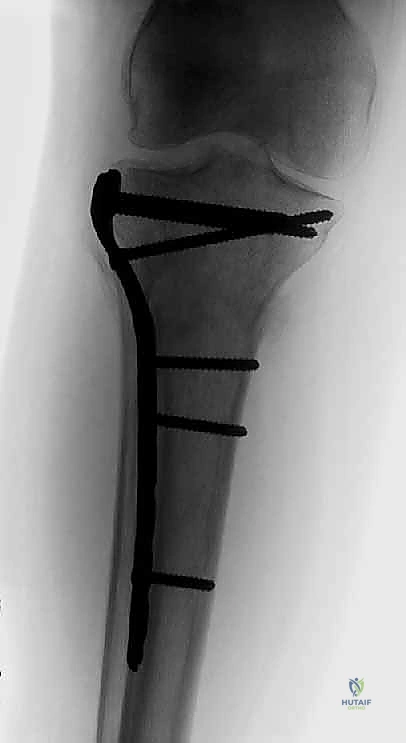

2. التثبيت الداخلي المفتوح (ORIF - Open Reduction and Internal Fixation)

هي العملية النهائية الحاسمة. تتضمن فتح الركبة، إعادة ترتيب الشظايا العظمية كقطع "البازل"، وتثبيتها باستخدام شرائح معدنية تشريحية ومسامير.

خطوات العملية الجراحية بالتفصيل (نهج الأستاذ الدكتور محمد هطيف)

العملية الجراحية لكسر ثنائي اللقمة تعتبر من "العمليات الكبرى" في جراحة العظام، وتستغرق عادة من 2 إلى 4 ساعات حسب درجة التفتت.

2. الشقوق الجراحية (النهج المزدوج - Dual Incision Approach)

لأن الكسر يشمل الجانبين الإنسي والوحشي، فإن شقًا جراحيًا واحدًا لا يكفي. يقوم الدكتور هطيف عادة بعمل شقين منفصلين لضمان عدم سلخ مساحة كبيرة من الجلد وتقليل خطر النخر:

* شق أمامي وحشي (Anterolateral Incision): للوصول إلى اللقمة الوحشية (التي تكون غالبًا مفتتة ومنخسفة).

* شق خلفي إنسي (Posteromedial Incision): للوصول إلى اللقمة الإنسية الك